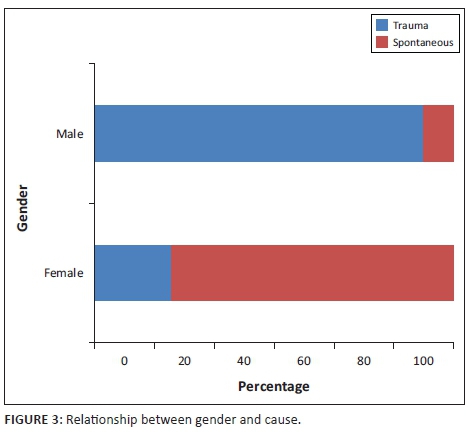

Initially, 38 patients were included in the study over the 13-year period. The mean age of the patients was 37.6 with a range of 9-94. The majority of patients were older than 30 years (60.52%). There were 24 male patients (63.16%) and 14 female patients (36.84%). In approximately two-thirds of the cases, the fistula was post-traumatic. A statistically significant difference was observed in the proportion of fistulas caused by trauma between men and women (91.67% vs. 21.4%, p < 0.001). This is presented in Figure 3.